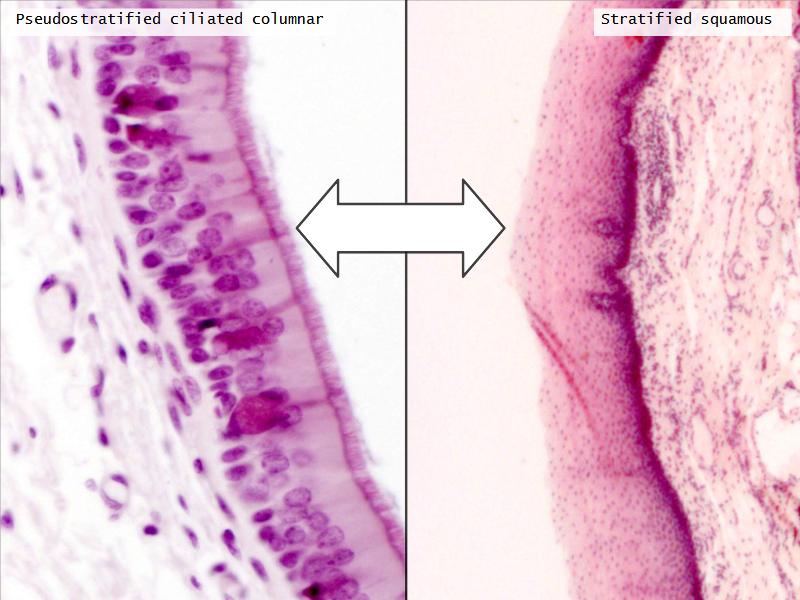

Epiglottis

Respiratory epithelium

- Pseudostratified

- Ciliated

- Columnar

- Epithelium with

- 4 Cells

- Ciliated columnar cells

- Non-ciliated columnar cells

- Goblet cells

- Basal cells